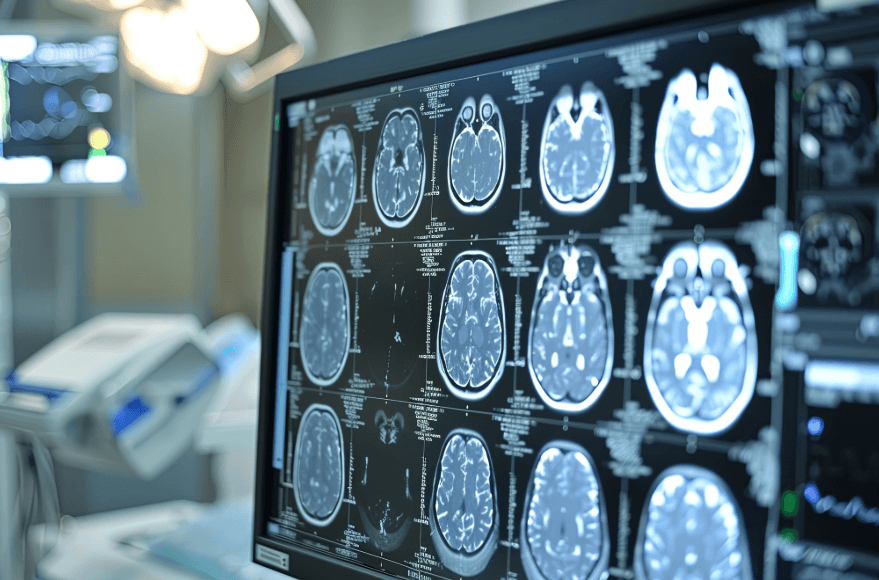

From a billing perspective, documentation requirements on the anesthesia record are the same as with any other anesthesia procedure. The appropriate ASA code depends on the particular circumstances of the diagnostic/therapeutic stroke-related procedure. Several codes may be in play. One such code is 01922, anesthesia for non-invasive imaging, with a base value of seven units, when a diagnostic CT of the head/brain is performed. As is typical for surgical cases, the anesthesia time reflects the continuum of care during which there is a relationship of dependence between patient and provider. Anesthesia times can vary from 45 minutes to three hours (three time units to 12 time units). Obviously, payment is a function of the patient’s insurance, and the majority of stroke patients are covered by Medicare, which has a significantly discounted rate.